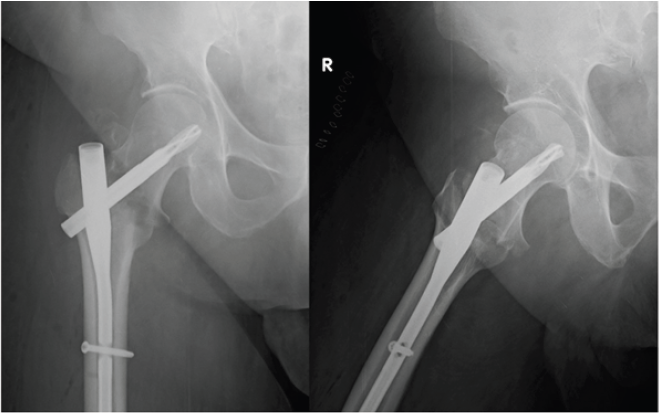

The patient was a 68 years old male, who had a car accident (Table 1). When he was admitted to the hospital, X-ray examination revealed a fracture of the surgical neck of left humerus and a fracture of the right femoral neck. He was treated with an intramedullary nailing of the femur (Proximal Femoral Nail Antirotation - PFNA system by ©DePuy Synthes) (Figure 1). The humerus fracture was managed conservatively with a shoulder immobilization for the first two weeks. The patient had an uneventful postoperative period, and he began immediately postoperative rehabilitation without weight bearing for the first two weeks. He continued his rehabilitation program in the following months, after hospital discharge, in a physiotherapy centre near his home. He placed on him from the third week, and two weeks later he has recovered to walk by himself, with the help of two crutches. At 6 months of follow-up, the Physicians (M.P., D.L.) noted a delayed healing of the fractures on X-ray (Figure 2), despite the good clinical condition of the patient, in fact he had no pain, and he was able to walk by himself without crutches or a limp. In addition, the patient missed the one-year follow-up due to pandemic emergency in March 2020. Two months after, he developed groin pain of the right hip and it was treated with a phone consultation by his general practitioner for a sciatic problem. Because of the persistent pain he called his surgeon who prescribed a new X-ray that revealed a superomedial migration of the proximal femoral blade, a phenomenon called cutin [12] (Figures 3 & 4). For this reason, the patient underwent a primary total hip arthroplasty with stem revision (©Lima Corporate) in October 2020 (Figure 5).

Figure 1: X-ray post-operative control.

Figure 2: Six months follow-up X-ray control.